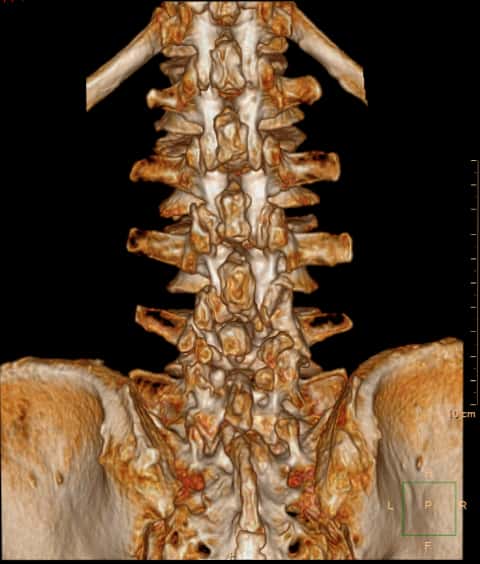

那么再看看患者的CT和MRI。问题并不简单。1997年因腰椎间盘突出,于北京XH医院行腰椎后路手术

腰椎退变增生

重建的片子上看不到太多的手术痕迹。

腰4/5水平,小关节及关节后方有大量的增生

腰4/5水平,小关节及关节后方有大量的增生。

多个腰椎小关节及关节后方有大量的增生。

断面可见明显的增生改变,提示腰椎不稳定。